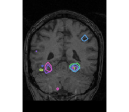

face

vs house

TV-l1

Graph-net

Social sparsity

Experiments outline a tradeoff between prediction accuracy and computation time. Fig. 1 displays the relative prediction accuracy and run time. TV- predicts best on average over the various classification tasks. However, it is followed closely by social sparsity which outperforms graph-net222All differences are significant in a Wilcoxon rank test.. The SVM performs much worse than the spatial sparsity, aside from the VBM data where we find that all models perform similarly.

Finally, an important aspect of the brain decoders is whether they segment well the brain regions that support the decoding. Such a question is hard to validate, yet there is evidence that TV- is a good approach [5]. Fig. 2 displays the decoder maps for the object-recognition tasks. For these tasks, we expect prediction to be driven by the functional areas of the visual cortex [27]. Indeed, the maps outline regions in known visual areas. The graph-net maps are much more scattered and less structured than the others. Conversely, the social sparsity maps are sparser and outline a smaller number of clusters.